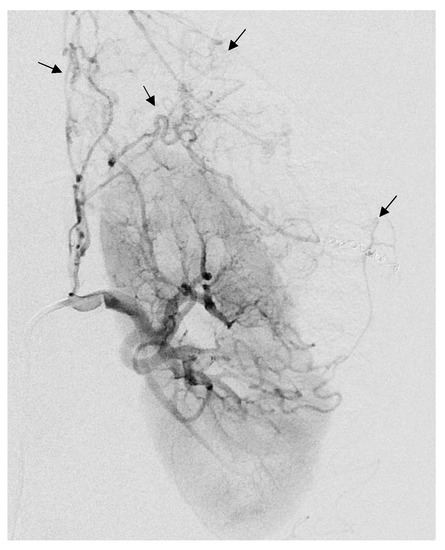

Figure 5.

Arteriogram showing a large left AML with anarchic vascularization (black arrows), as part of a Tuberous sclerosis complex in a 32-year-old patient.

Three patients had been embolized with other embolization agents before Onyx. One patient, with tuberous sclerosis complex (Figure 5), had three previous embolization with microparticles (700 and 900 microns) and supplemental coil occlusion before embolization with Onyx. One other patient had a previous embolization with 900-micron microparticles. Finally, another patient had been embolized with two micro-coils in another center.